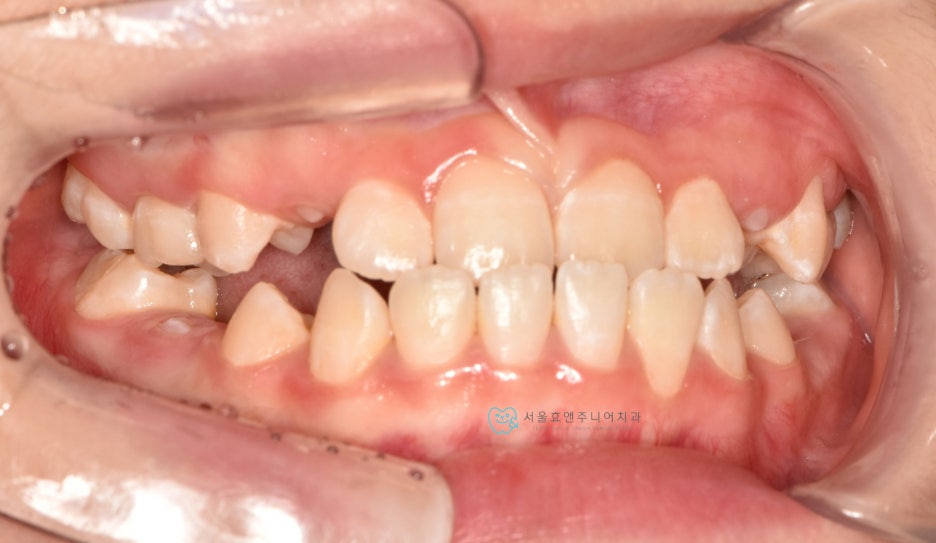

다음 케이스입니다.

너무 예쁜 10세 11개월의 여자친구인데 반대교합이 있네요.

초진사진입니다. 앞니의 반대교합이 보입니다.